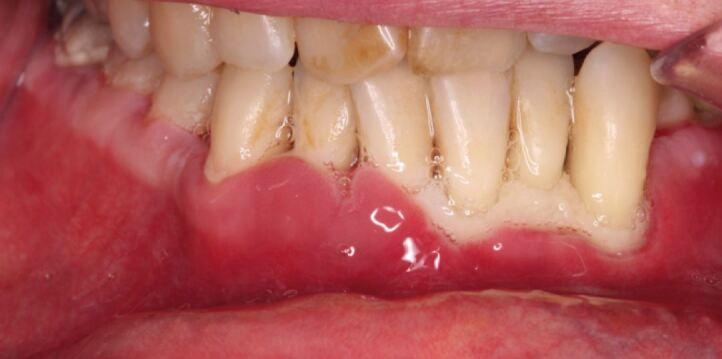

'Necrotising periodontal diseases' is an umbrella term for necrotising gingivitis, necrotising periodontitis, necrotising stomatitis and noma. These rapidly destructive conditions are characterised by pain, interdental ulceration and gingival necrosis which, if left untreated, can result in osteonecrosis. Research indicates that patients with a history of alcohol misuse are at an increased risk of malnutrition, which negatively affects the immune response and predisposition to necrotising periodontal diseases. This article will discuss that osteonecrosis of the alveolar bone does not exclusively occur in association with antiresorptive medications, but can occur as a severe form of necrotising gingivitis. In this article, we will describe two cases to highlight the occurrence, presentation and management of necrotising periodontal diseases secondary to alcohol misuse.

'坏死性牙周病'是坏死性龈炎、坏死性牙周炎、坏死性口炎和口底蜂窝织炎的统称。这些迅速破坏性的疾病的特征是疼痛、牙间溃疡和牙龈坏死,如果不治疗,可能导致骨坏死。研究表明,有酒精滥用史的患者更容易出现营养不良,这会对免疫反应和发生坏死性牙周病的倾向产生负面影响。本文将讨论牙槽骨骨坏死不仅与抗吸收药物有关,还可能作为严重的坏死性龈炎发生。在本文中,我们将描述两例病例,以强调酒精滥用引起的坏死性牙周病的发生、表现和治疗。